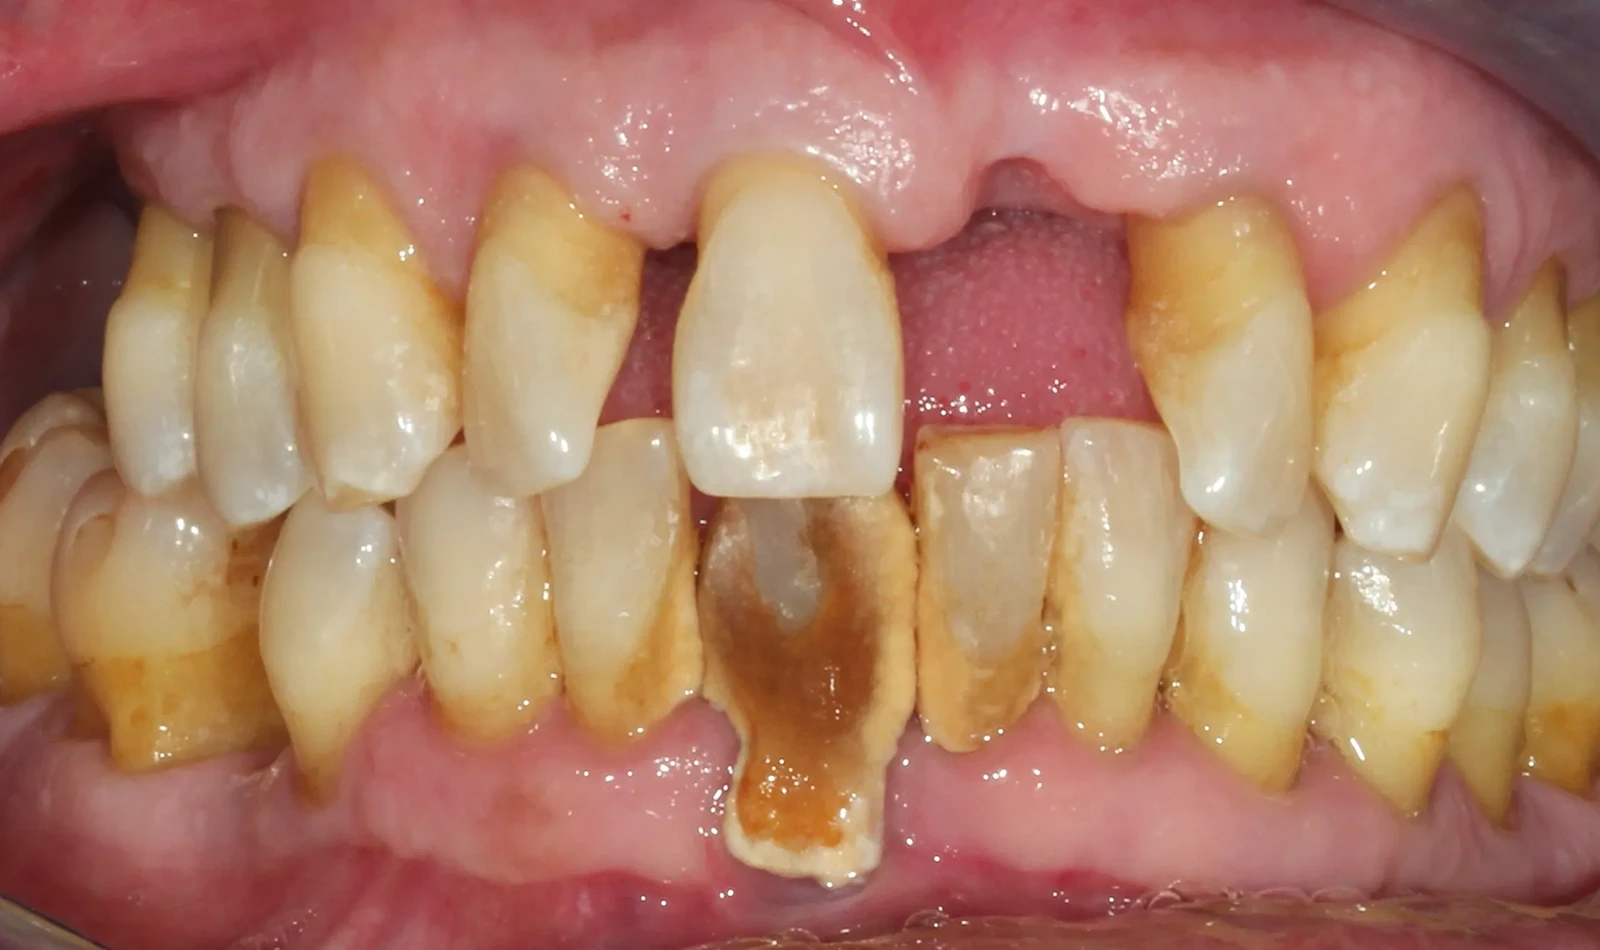

Paciente #2:

De 61 años nos visita con dientes dañados por caries y una prótesis antigua que ya no podía utilizar. Gracias a la planificación digital y la cirugía guiada, realizamos las extracciones y colocamos implantes con una prótesis fija el mismo día. Recuperó su sonrisa y la confianza de inmediato.